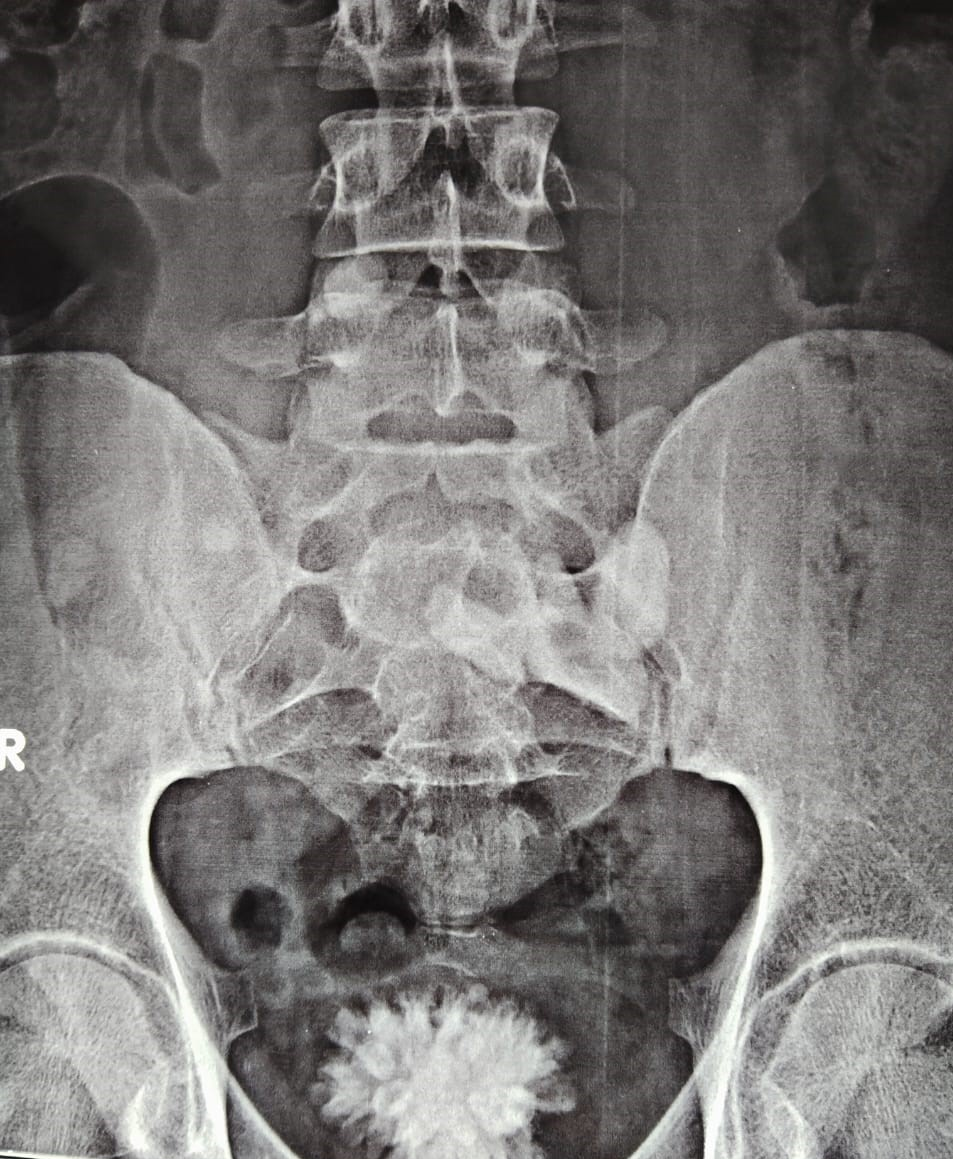

A 27-year-old male presented with suprapubic pain, dysuria, and intermittent haematuria for 7 days. X-ray KUB revealed a bladder calculus, while ultrasound suggested a pelvic fused kidney with renal stones (Figure 1).

Figure 1:- Large Vesical calculus seen in X-Ray KUB.

Contrast-enhanced CT KUB demonstrated a single, flat, discoid renal mass located in the pelvic cavity, consistent with a pancake kidney, showing complete fusion of both renal units across the midline with absent renal ascent and malrotation. The collecting systems were anteriorly oriented and the ureters were observed to be short. Within the fused renal moiety, two non-obstructing calculi were identified, measuring approximately 10.8 × 11.7 × 16.3 mm and 7 × 9 × 9.5 mm. There was no associated calyceal dilatation or hydronephrosis. Additionally, a large hyperdense vesical calculus was noted within the urinary bladder (Figure 2).

Figure 2: CT KUB suggestive pelvic kidney with large renal calculi and bladder calculus.